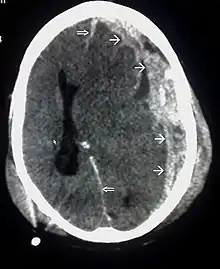

| CT scan showing cerebral contusions, hemorrhage within the hemispheres, subdural hematoma, and skull fractures[2] | |